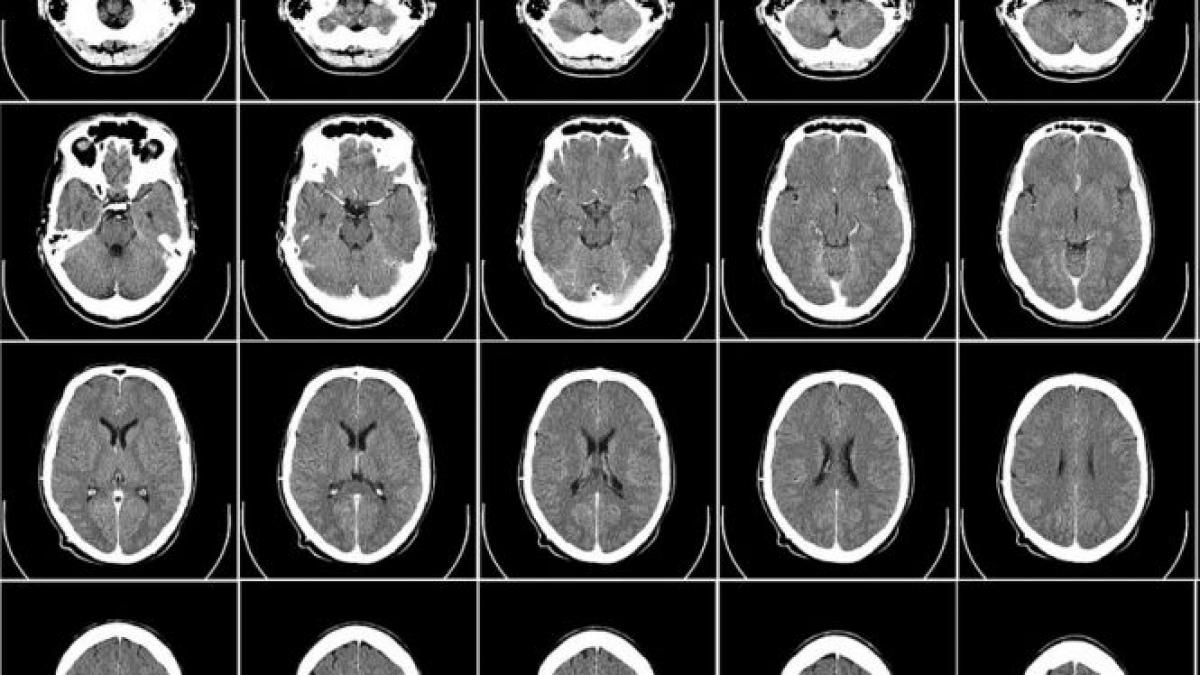

Vârsta până la care creierul uman continuă să se dezvolte. Se maturizează complet cu mult după 18 ani15 Aug